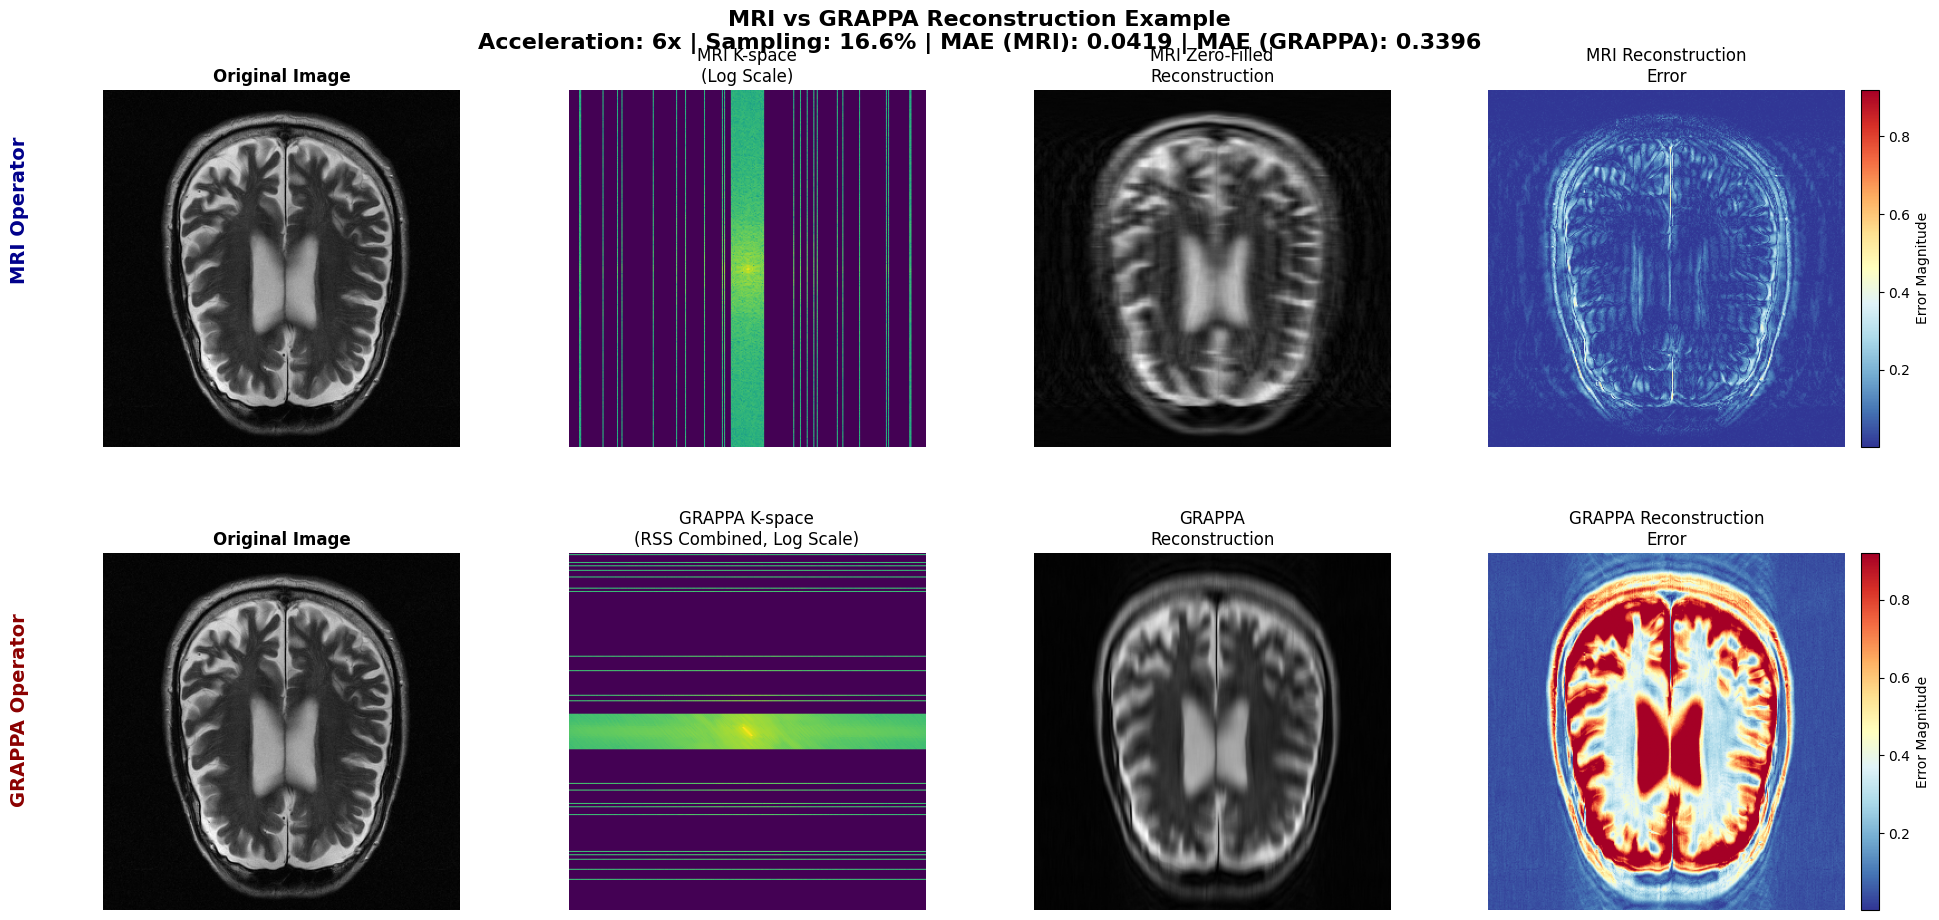

Research Projects IGLU Integrated Gaussian Linear Unit Convolutional Nearest Neighbors Unifying Convolution and Attention through k-NN ConvNN-Attention Unified Convolution-Attention operation for Vision Transformers Parallel qMRI Reconstruction Parallel qMRI Reconstruction from 4x Accelerated Acquisitions Cochlear Project Structure and Process-Level Lexical Interactions in Memory Search Ungated Research Public Web Platform for Economics Working Papers Writing Samples NSF GRFP Statements Research Plan and Personal Statement for NSF Graduate Research Fellowship Program (GRFP) 2025